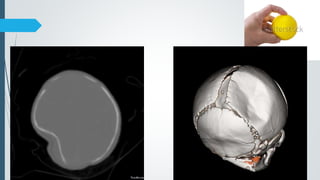

Ping pong/ Pond skull fracture

 called a 'ping pong' fracture because it resembles a ping

pong ball that has been indented inwards with a finger.

 Depressed skull fracture of the infant skull caused by inner

buckling of the calvarium.

 Fracture line is not visualized radiologically.

 It is seen in newborns because of the soft and resilient nature

of their bones (like greenstick fracture of long bones)

 Periosteum and dura are intact

 Pathology – birth trauma or postnatal blunt traumas